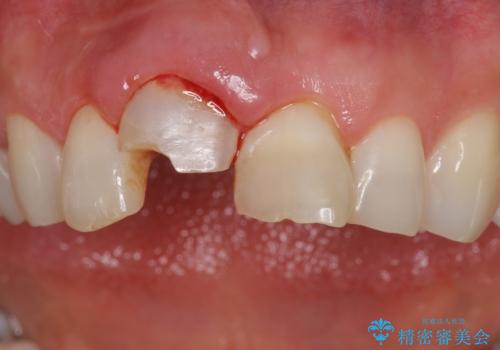

- 転んで前歯が折れたとのことで来院されました。

検査の結果、歯は大きく折れておらず、骨の中に埋め込まれていた状態であったため、部分矯正で歯を引っ張り出していきます。